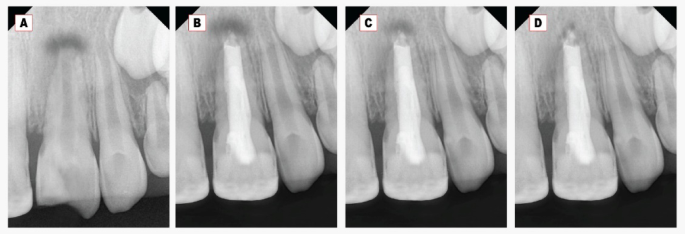

Regarding the periapical radiolucency (PAR) area, a significant decrease in the PAR area was found at all follow-ups within each group Figs. 2 and 3. At twelve months, the mean PAR area in the Well-Root PT group was (0.14 ± 0.08) compared to (2.3 ± 0.9) in the MTA group. A highly statistically significant difference was observed between the two tested groups at all follow-up periods (p < 0.001) as represented in Table 3.

Concerning the periapical bone radiodensity, there was a significant increase in the bone radiodensity at 6- and 12-month follow-up periods within each group, as shown in Table 3 and Figs. 2, 3. The mean periapical bone radiodensity in the Well-Root PT group was (178.2 ± 5.4) compared to (164.8 ± 9.4) in the MTA group at twelve-month follow-up. A highly statistically significant difference was found between the MTA and Well-Root PT groups at all follow-up periods (p < 0.001). Using the Bonferroni test, each observation was significantly different from the baseline and the other observation (p < 0.001).